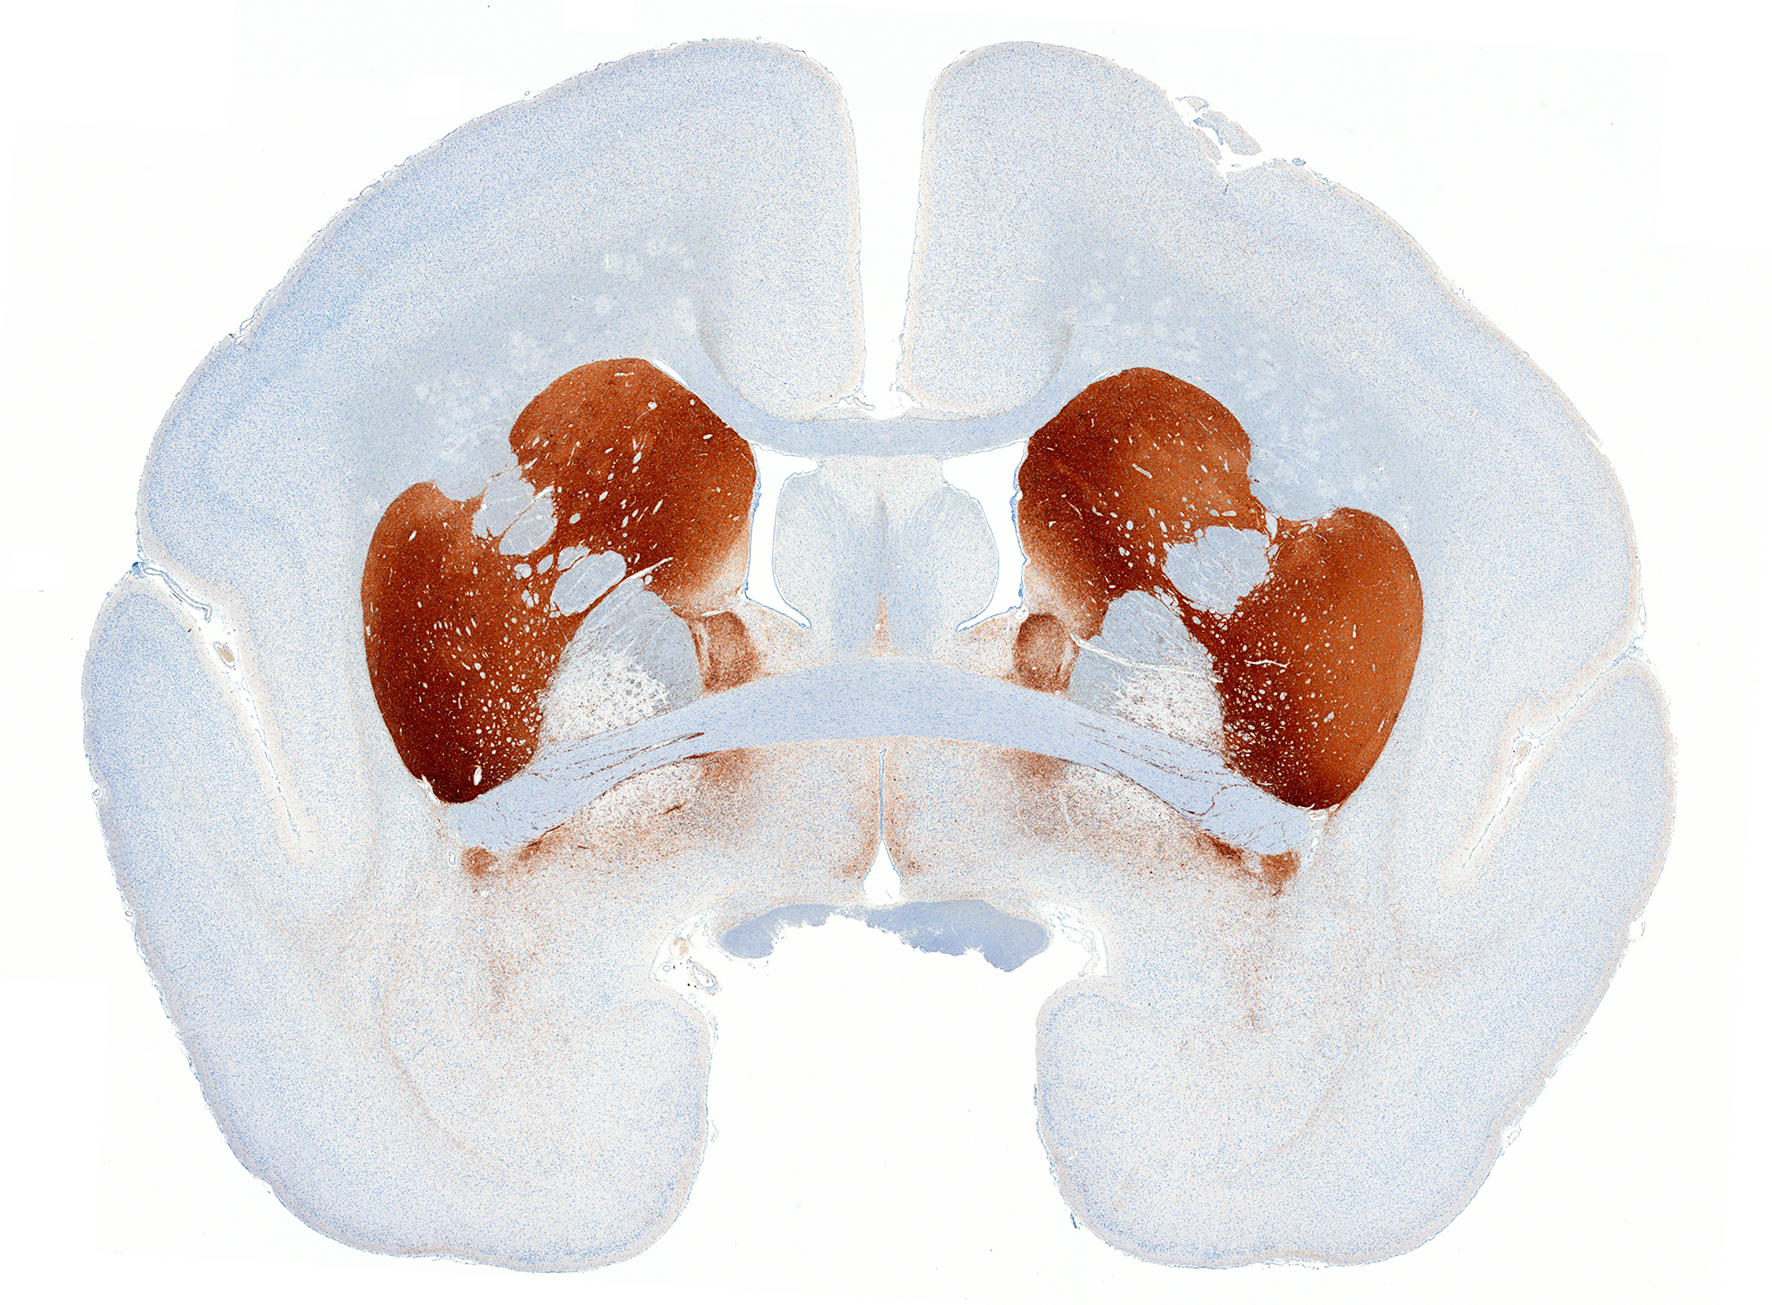

Anti-TH staining (immunostaining) (marmoset brain)